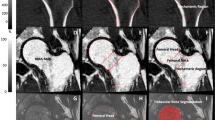

QCT scanning and analysis

At the second examination day, lumbar spine and the left hip were scanned and analyzed using four‐row detector CT system (Sensation; Siemens Medical Systems, Erlangen, Germany), as previously described [18]. Briefly, bone mineral reference phantom (three-sample calibration phantom, Image Analysis, Columbia, KY, USA) was placed under the participants’ spine and hips and scanned simultaneously for calibration. Helical studies were done at lumbar spine (L1 and L2 vertebrae) and hip (proximal femur from 1 cm superior to acetabulum to 3–5 mm inferior to lesser trochanter) at following parameters: 120 kVp, 150 mAs for spine, and 140 mAs for hip, 1-mm slice thickness, and pitch = 1.

For each trabecular, cortical, and integral region of interest, volumetric BMD (vBMD; g/cm3), as well as a simulated areal BMD (g/cm2) obtained by dividing the BMC by the projected area of the region of interest on the coronal plane, was calculated from QCT data. The vertebral regions of interest included the vertebral centrum and another region comprising both the centrum and the spinous processes, the latter region being used to derive the simulated DXA. Cross-sectional areas (CSAs) and indices of compressive strength of the femoral neck and mid-vertebrae were estimated as previously described [18]. Femoral neck section modulus (a measure of bending strength) was computed at the femoral neck cross section as an elastic-modulus weighted polar moment of inertia divided by the neck width and normalized by nominal cortical elastic modulus. In addition, we also computed the cortical index (ratio of the femoral neck cortical volume to the total bone volume (cvol/ivol)), as a measure of the integrity of the proximal femoral cortex, as described by Lang et al. [19].